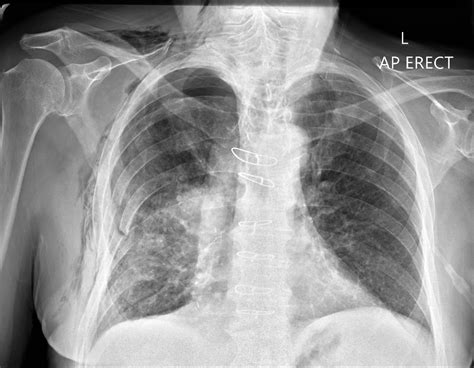

Diagnosing Pneumothorax with Chest X-Ray

Chest X-rays are the primary imaging modality used to diagnose pneumothorax. They provide a clear view of the lungs and pleural space, allowing radiologists to identify the presence of air. The key features to look for in a pneumothorax in X-ray include:

There are different types of pneumothorax, each with its own characteristics on an X-ray:

Secondary pneumothorax occurs in patients with underlying lung disease, such as COPD or cystic fibrosis. On an X-ray, it may show additional findings related to the underlying condition, such as bullae (air-filled spaces) or emphysematous changes.